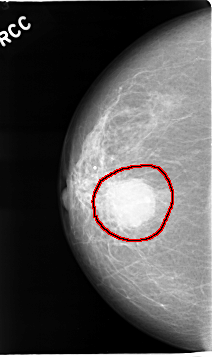

C_0051_1.RIGHT_CC

RIGHT_CC LINES 4640 PIXELS_PER_LINE 2752 BITS_PER_PIXEL 12 RESOLUTION 50 OVERLAY

FILE: C_0051_1.RIGHT_CC.OVERLAY

TOTAL_ABNORMALITIES 1

ABNORMALITY 1

LESION_TYPE MASS SHAPE LOBULATED MARGINS MICROLOBULATED

ASSESSMENT 5

SUBTLETY 5

PATHOLOGY MALIGNANT

TOTAL_OUTLINES 1

BOUNDARY